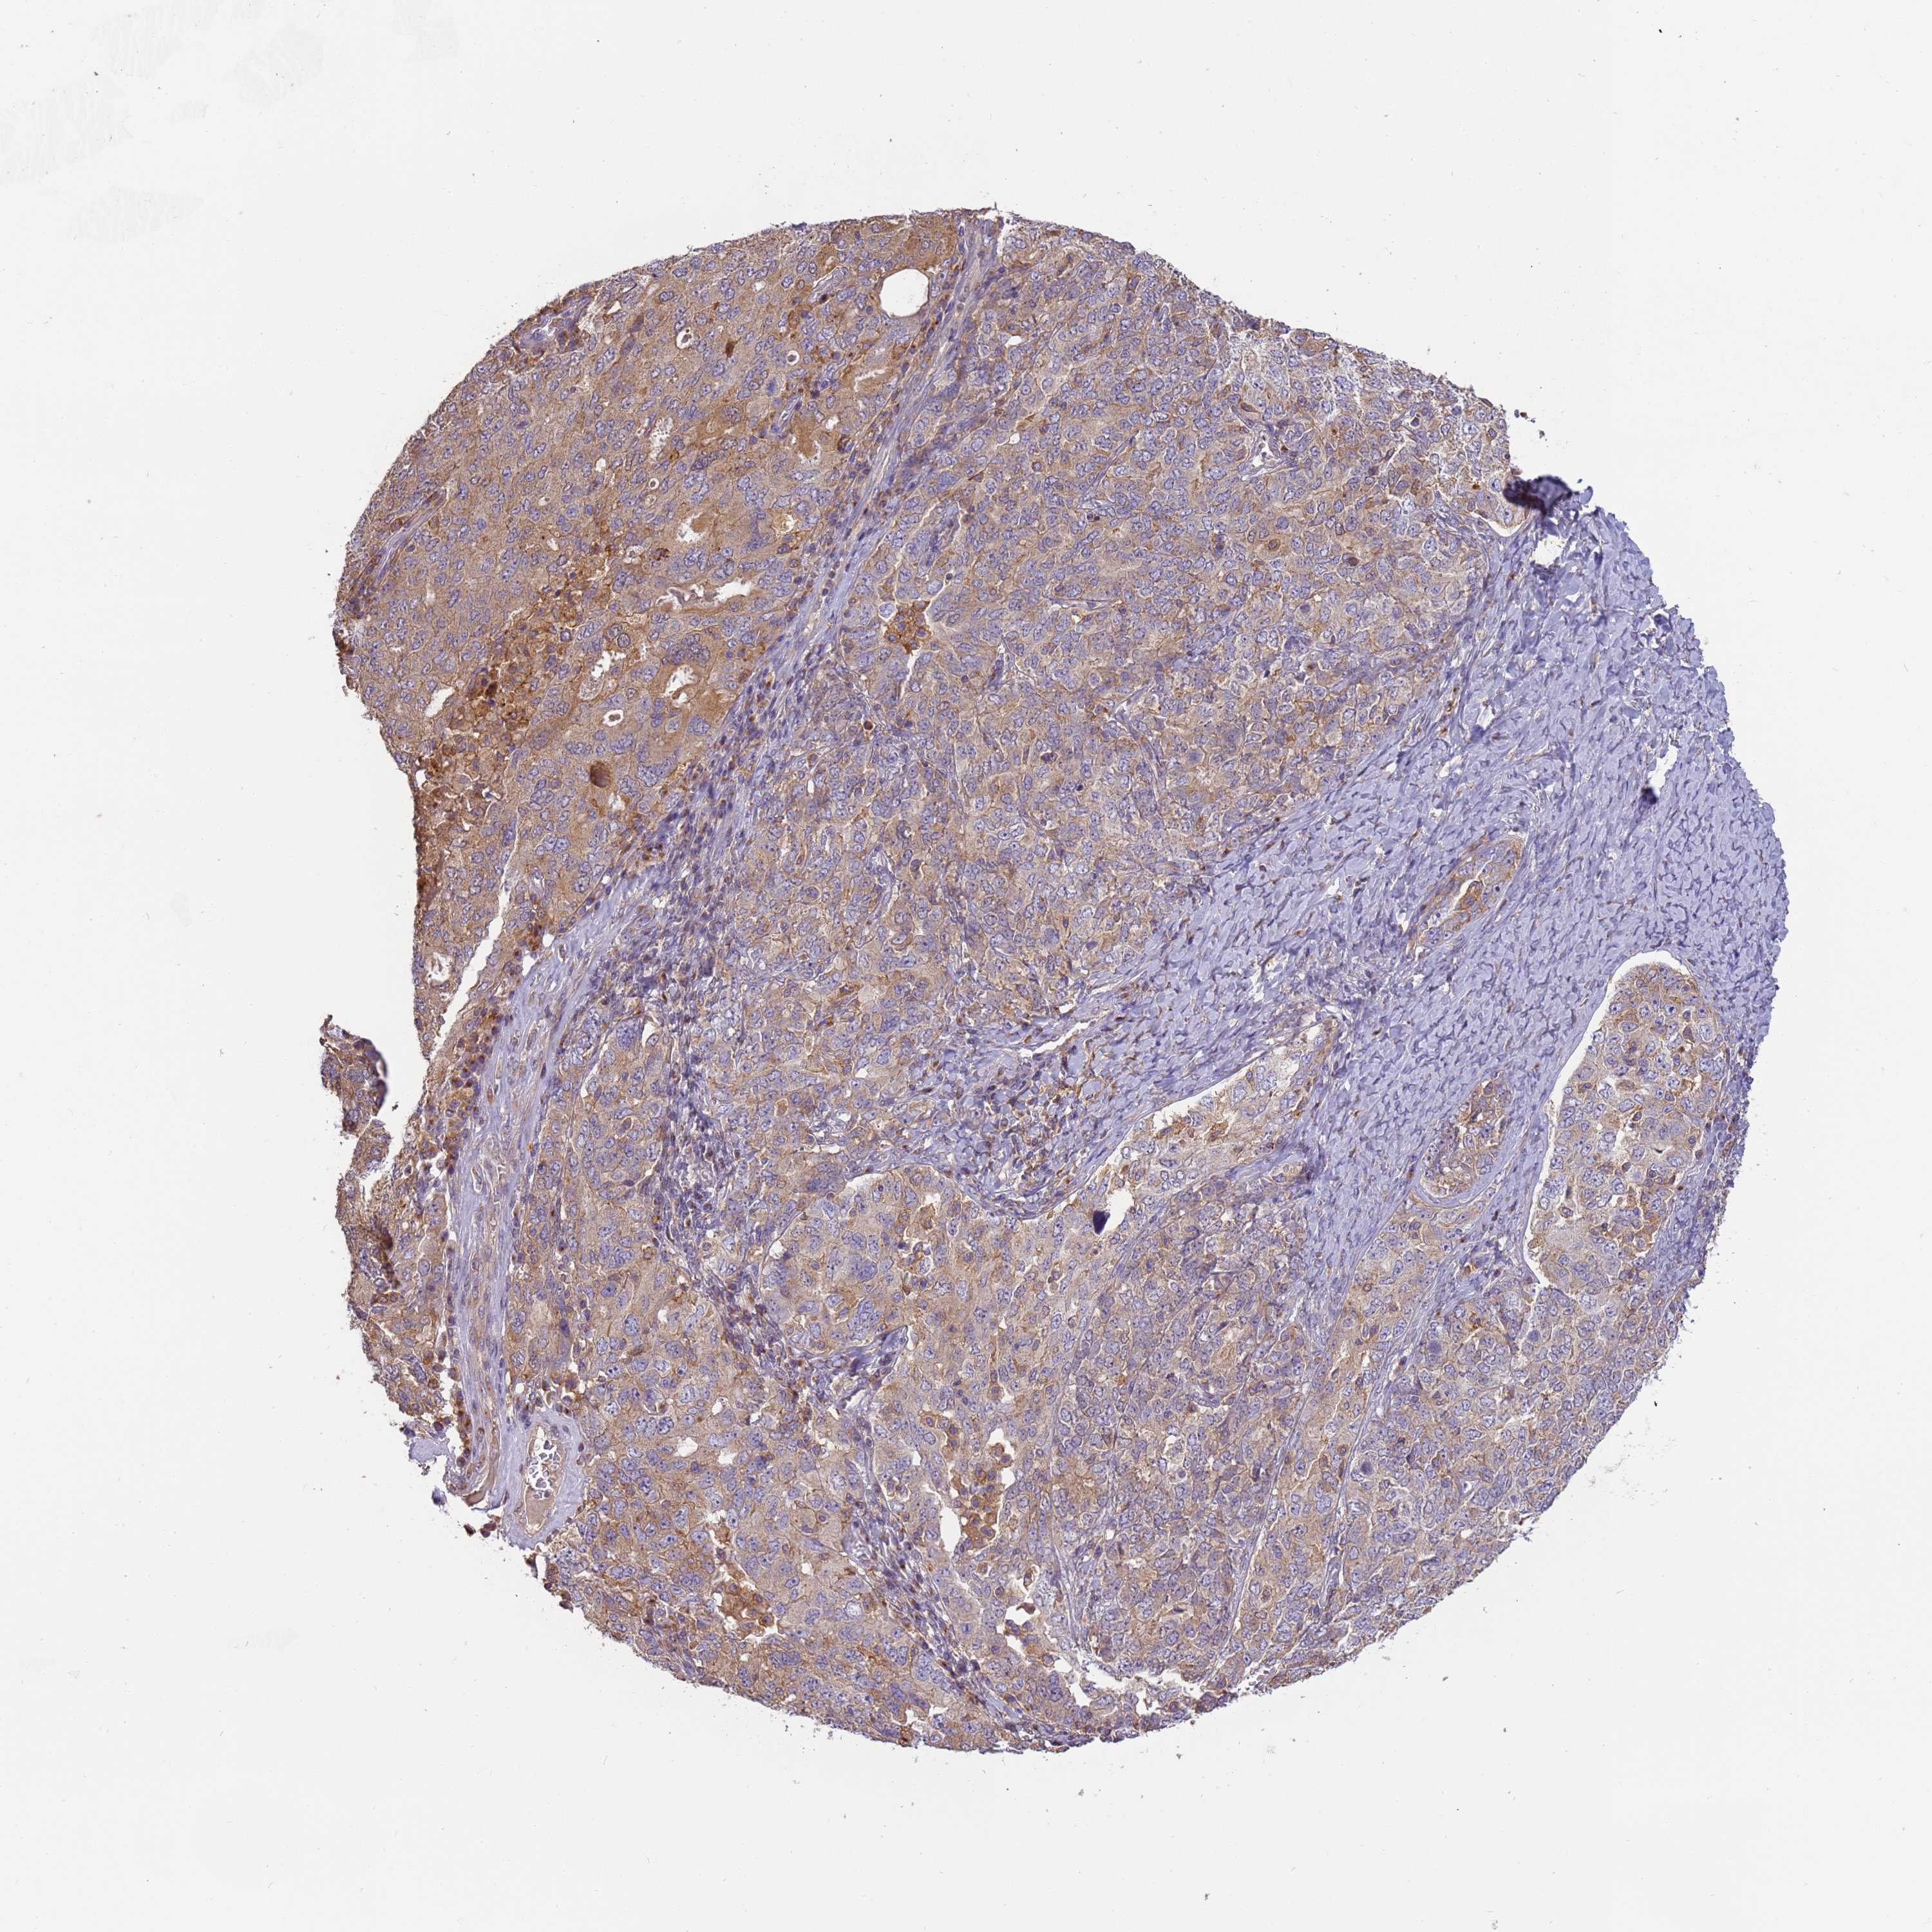

OVARIAN CANCER - Protein expressioni

A mouse-over function shows sample information and annotation data. Click on an image to view it in a full screen mode. Samples can be filtered based on level of antibody staining by selecting one or several of the following categories: high, medium, low and not detected. The assay and annotation is described here.

Note that samples used for immunohistochemistry by the Human Protein Atlas do not correspond to samples in the TCGA dataset.

Antibody stainingi

Antibody staining in the annotated cell types in the current human tissue is reported as not detected, low, medium, or high, based on conventional immunohistochemistry profiling in selected tissues. This score is based on the combination of the staining intensity and fraction of stained cells.

Each image is clickable and will lead to virtual microscopy that enables deeper exploration of all samples and also displays staining intensity scores, fraction scores and subcellular localization as well as patient and tissue information for each sample.

Antibody HPA040445

Antibody CAB034464

Staining

High

Medium

Low

Not detected

Intensity

Strong

Moderate

Weak

Negative

Quantity

>75%

75%-25%

<25%

None

Location

Nuclear

Cytoplasmic/membranous

Cytoplasmic/membranous,nuclear

Cystadenocarcinoma, serous, NOS